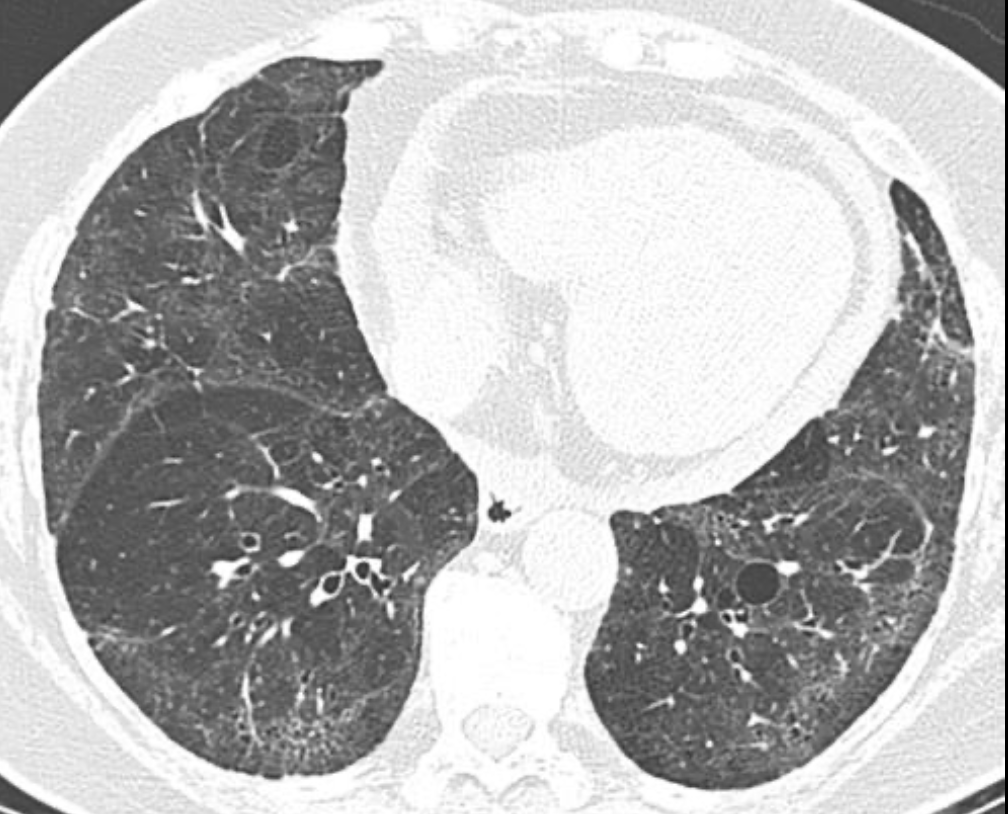

A

Patrón intersticial reticular